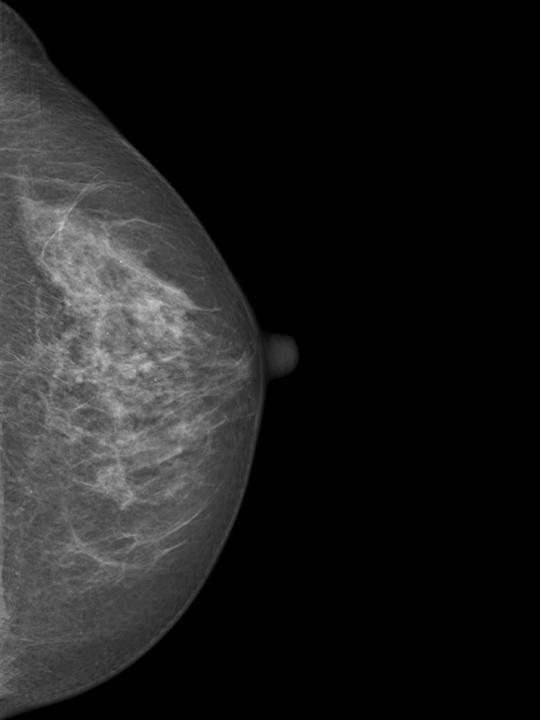

Mammography Wikipedia from upload.wikimedia.org Even if you have a lump in only one breast, pictures will be taken of both breasts. However, in rare cases, breast cancer can be the cause of gynecomastia so, a full mammographic investigation is always necessary. Dense breast tissue appears solid. 1 the gray areas correspond to normal fatty tissue, while the white areas are normal breast tissue with ducts and lobes. This overlapping tissue can cause the resulting image to look like cancer. After a mammogram that didn't show anything, and a sonogram that found the lump, i was diagnosed with stage 2 breast cancer. This is why you should always talk to your doctor if you notice an unexplained change in the size of a breast. We'll show you breast cancer pictures to help you identify any physical traits of the condition.

Essentially, mammograms turn a 3d object into a 2d object. This is why you should always talk to your doctor if you notice an unexplained change in the size of a breast. What does the doctor look for on a mammogram? cancer.org. A screening mammogram is performed at regular intervals to check for breast cancer in women who have no signs or symptoms of the disease. Bright spots on a mammogram that look like potential tumors could turn out to be overlapping tissues or a blood vessel folding over on itself, friedewald said. To license this video for patient education or content marketing, visit: What does breast cancer look like? This overlapping tissue can cause the resulting image to look like cancer. Finding breast lumps and seeing change in the size and shape. Screening mammograms have been used since the 1980s. Digital breast tomosynthesis (tomo), also known as 3d mammography, is a revolutionary new screening and diagnostic breast imaging tool to improve the early detection of breast cancer. Ultrasound characterization of breast masses. indian journal of radiology and imaging. Calcifications are calcium deposits within the breast tissue and they look like small white spots.

Moose & doc breast cancer, 21 may 2018. We'll show you breast cancer pictures to help you identify any physical traits of the condition. Normal breast tissue can look 100,000 different ways on a mammogram. Finding breast lumps and seeing change in the size and shape. Dense breast tissue appears solid. Essentially, mammograms turn a 3d object into a 2d object. American cancer society, 9 oct 2017. That makes it easy to detect abnormalities, which generally show up as white. A 3d mammogram is used to look for breast cancer in people who have no signs or symptoms. More importantly, the overlap can obscure small breast cancers. A screening mammogram is performed at regular intervals to check for breast cancer in women who have no signs or symptoms of the disease. Several patterns of calcifications are seen with dcis, including: Breast cancer and some noncancerous (benign) breast conditions can appear white on a mammogram.

More Breast Cancers Detected With 3d Mammography National Breast Cancer Foundation Nbcf Donate Online from 1o2l7w1aqqrk1f987e40vzis-wpengine.netdna-ssl.com This overlapping tissue can cause the resulting image to look like cancer. Several patterns of calcifications are seen with dcis, including: The look of breast cancer on a mammogram a tumor or lump will appear as a focused white area on the mammogram. Most screening mammograms include two views of each breast taken from different angles. Specialist doctors (radiologists) trained to interpret mammograms can identify any abnormal areas, masses or calcium. What does breast cancer look like on a mammogram? A tumor that is benign, it is not a health problem and it may not grow or change shape. Ultrasound characterization of breast masses. indian journal of radiology and imaging.

Breast cancer and some noncancerous (benign) breast conditions can appear white on a mammogram. This overlapping tissue can cause the resulting image to look like cancer. Diagnostic mammograms involve taking more views than screening mammograms. It's so important to listen to the messages our bodies are telling. A number of studies have found that 3d mammograms find more cancers than traditional 2d mammograms and also reduce the number of false positives. Ultrasound characterization of breast masses. indian journal of radiology and imaging. Even if you have a lump in only one breast, pictures will be taken of both breasts. Finding breast lumps and seeing change in the size and shape. 1 the gray areas correspond to normal fatty tissue, while the white areas are normal breast tissue with ducts and lobes. A false positive is when a mammogram shows an abnormal area that looks like a cancer but turns out to be normal. Breast cancer can appear as a spiculated mass, cluster of tiny calcifications, smoothly marginated mass, area of subtle distortion or be invisible on. Macrocalcifications, which look like small white dots on a mammogram. One advantage of ultrasound technology is that it allows substantial freedom in obtaining breast images from any orientation.